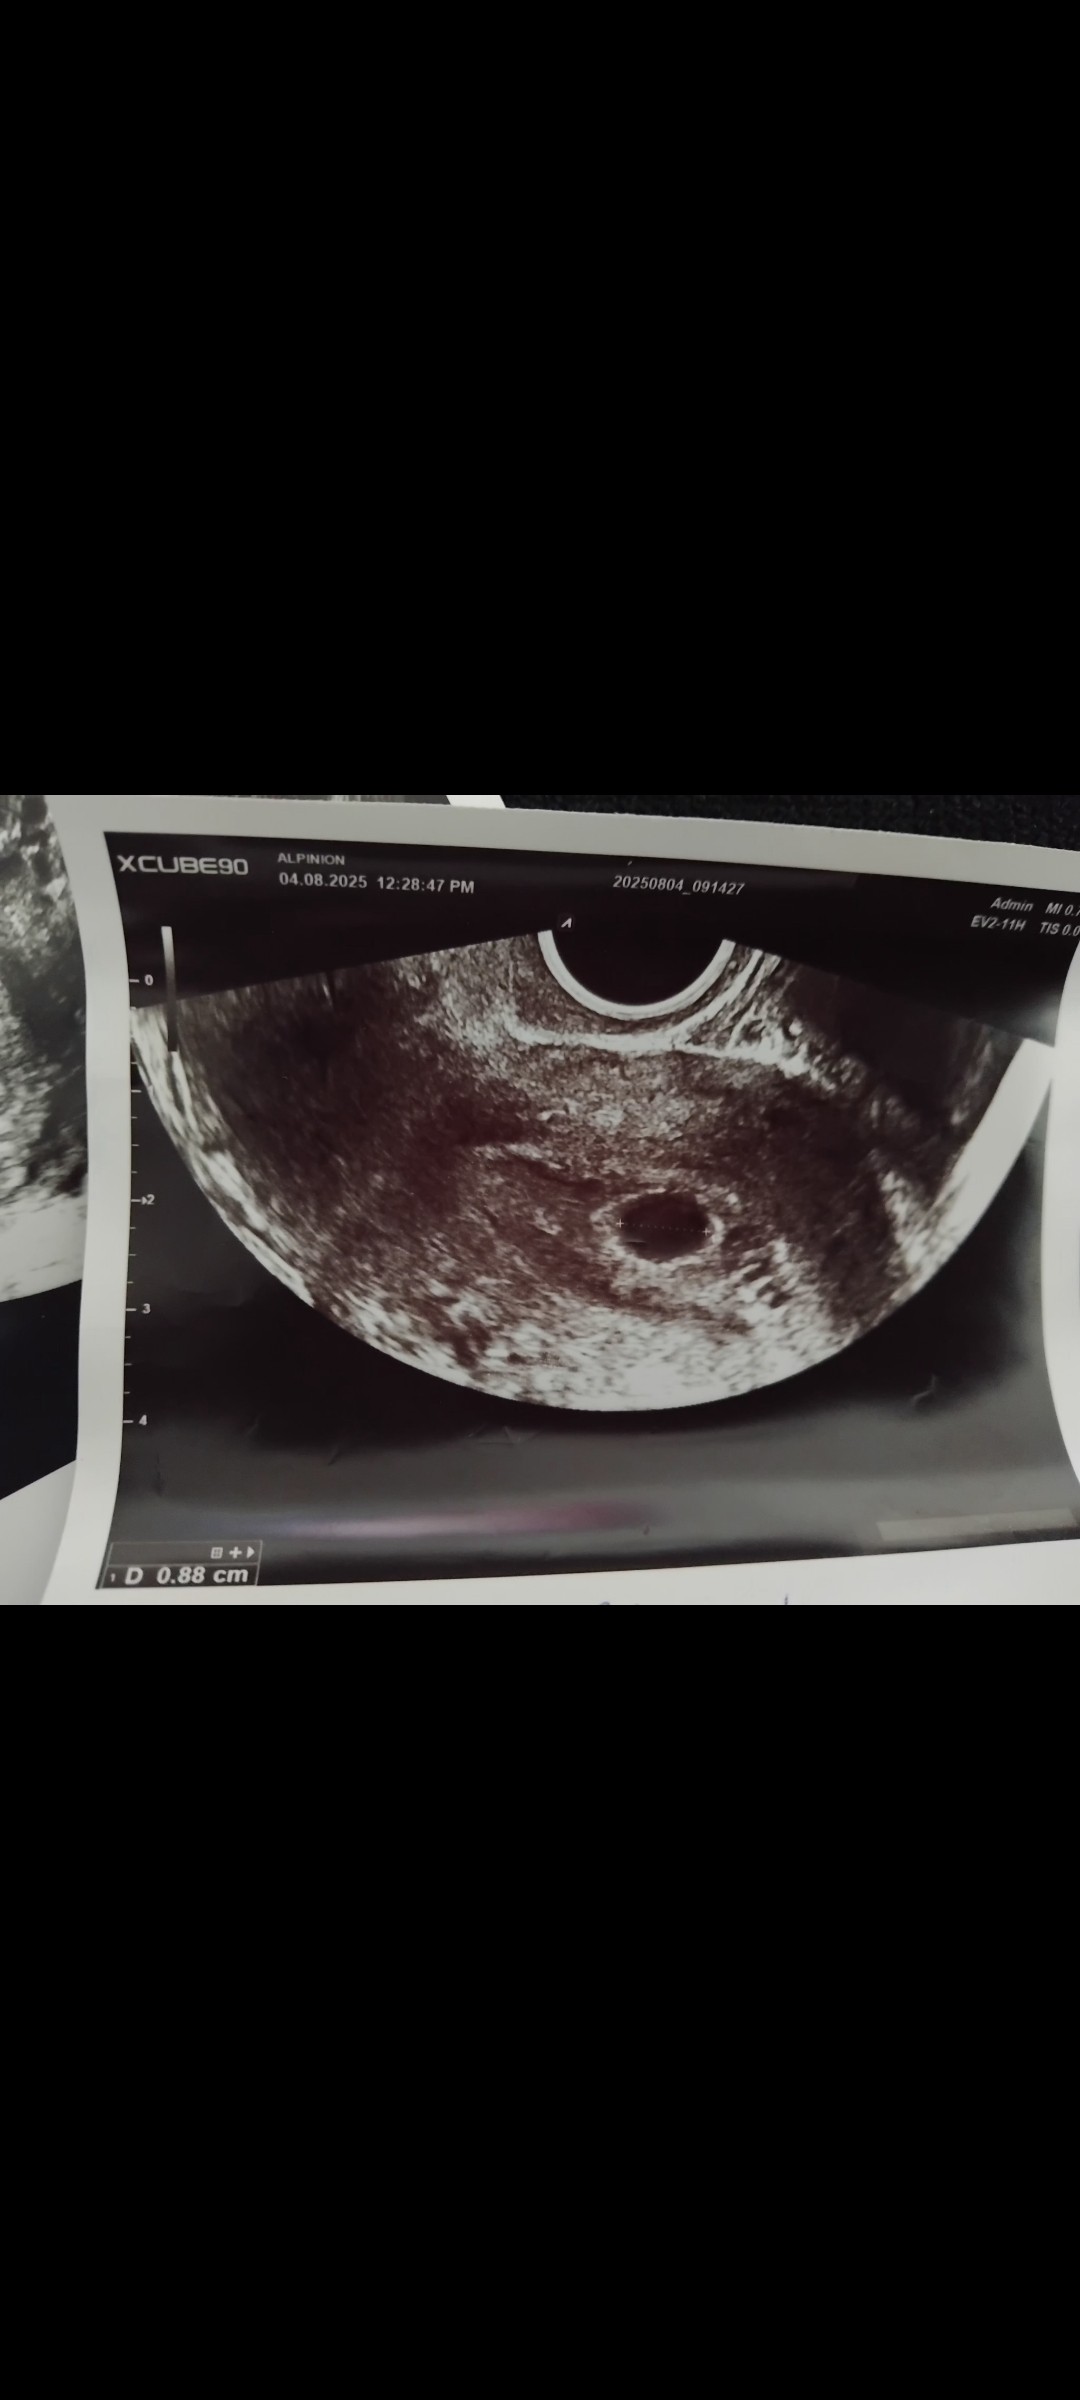

Kolejna wizyta 4 sierpnia pęcherzyk ciążowy 0.88 mm w międzyczasie jednego dnia miałam upławy takie jakby koloru zabarwionego na brązowo było tego na prawdę malutko 2 Może 3 razy lekko zauważalne na papierze